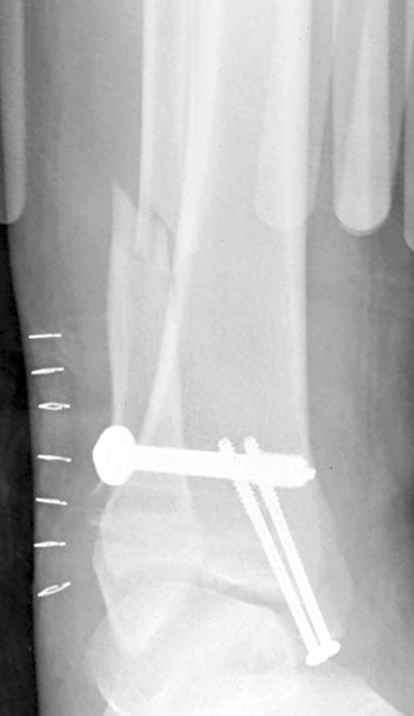

Ниже рентгенограммы

Операция 29 июля

Через месяц

Боковой через месяц

15 ноября прямой

15 ноября боковой

15 ноября трехчетвертной

12 января прямой

12 января боковой

12 января трехчетвертной

Риторический вопрос - в каком руководстве рекомендован такой способ остеосинтеза наружной лодыжки?

Очевидно, такой результат операции был запрограммирован. При невосстановленной длине и практически нефиксированной малоберцовой кости (этот кортикальный винт - как карандаш в стакане), при неустраненном подвывихе, невправленной и тоже нефиксированной внутренней лодыжке нет стабильной вилки сустава. Если такую операцию сделать даже сразу, а не через 4 месяца, то результат ожидаем

тот же.

Если до сих ничего не сделано, с артродезом сустава в данный момент я бы повременил, на выставленных январских снимках хорошо сохранившийся сустав, а в "мортиз" (трехчетвертной) и на боковых снимках не менее 5 мм укорочение малоберцовой кости. Косые переломы лучше фиксировать пластинами, как то мы разбирали случай, где было отмечено, что это закон "таранная кость всегда следует за малоберцовой".